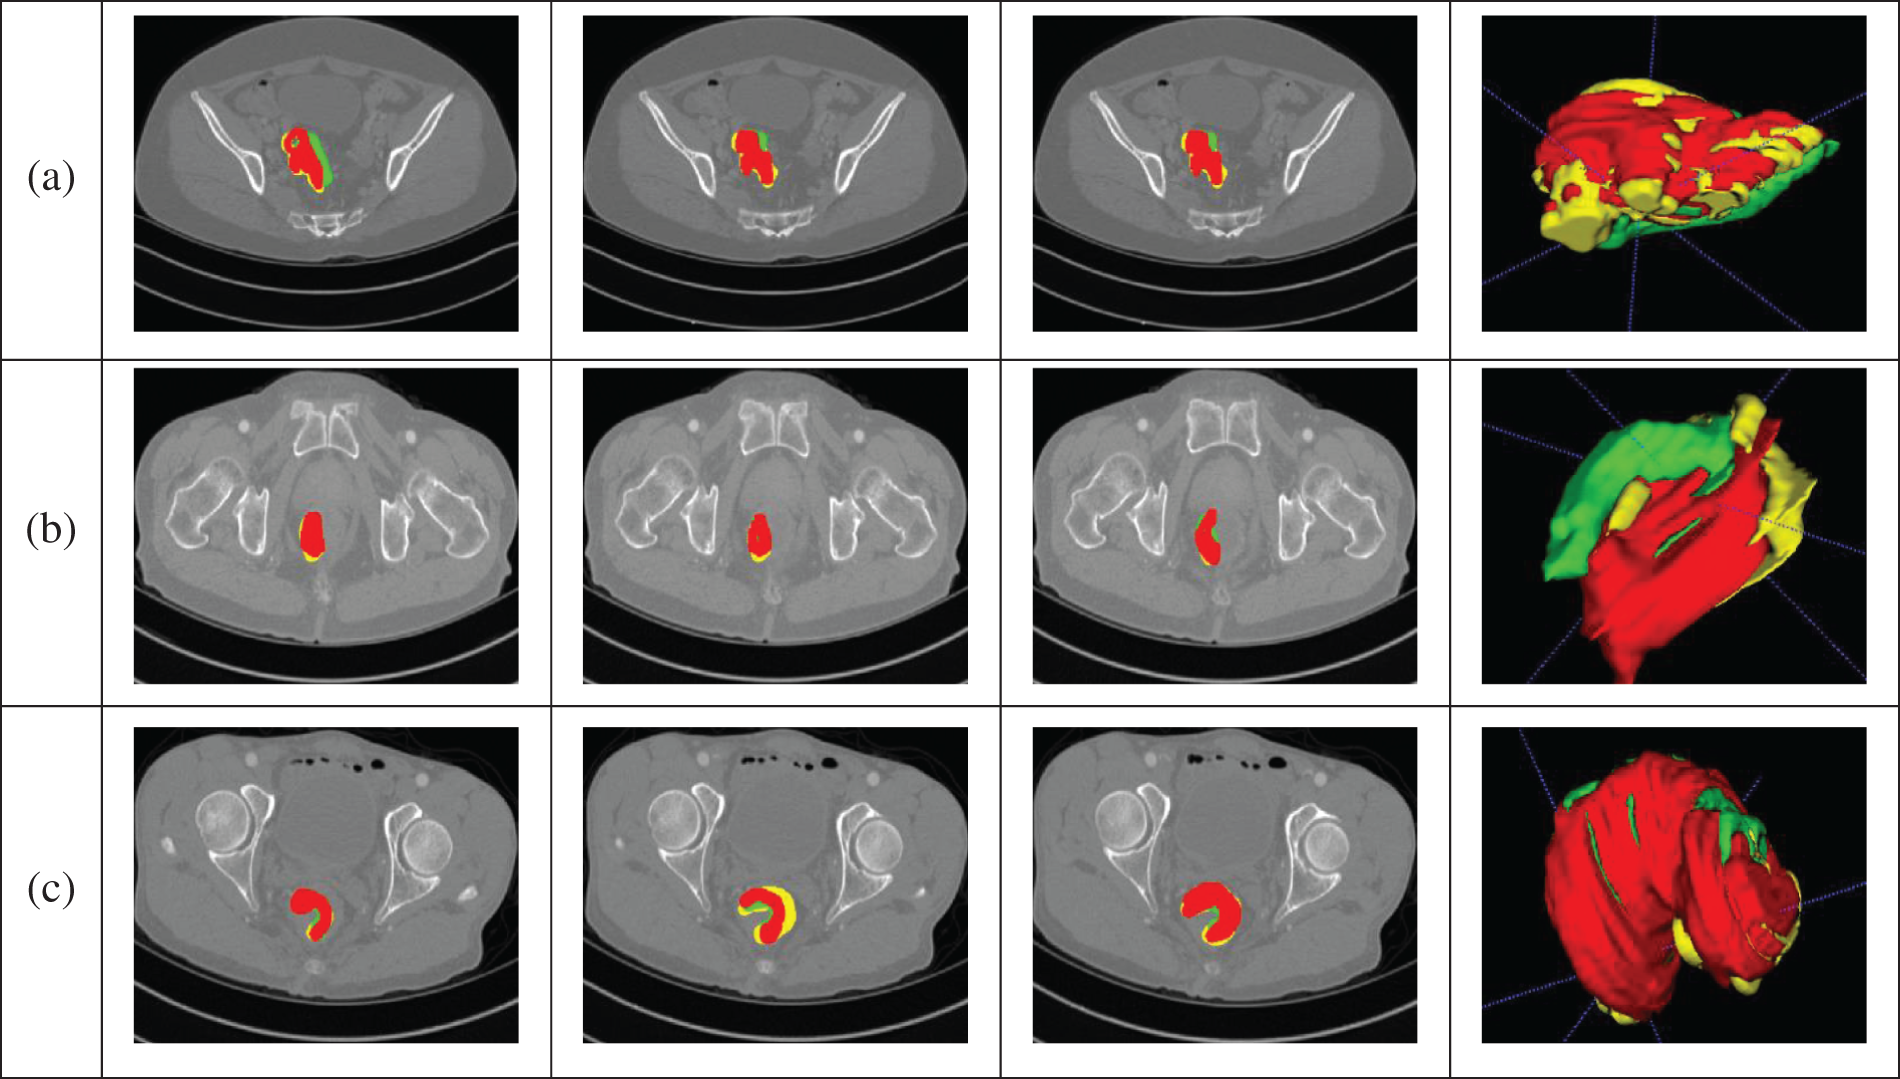

The segmentation results obtained by the algorithm presented in this article are depicted in Fig. 8, demonstrating its ability to accurately segment CRC. Data from the portal venous phase are marked in red, data from the delayed phase in green, and data from the arterial phase in yellow. The three-dimensional images provide a clear visual representation of the cancer’s morphology, showing a relatively complete structure, and validating the algorithm’s effectiveness. The final segmentation proportions for portal, arterial, and delayed phase data are 70%:17%:13%, respectively, aligning closely with the physicians’ annotations and indirectly confirming the algorithm’s efficacy. Fig. 8a shows the segmentation results from all three phases intertwined. Fig. 8b demonstrates that arterial and delayed phase data are distributed at the ends of the CRC region, with portal venous phase data predominantly concentrated in the middle, indicating that images from different phases represent distinct regions, facilitating a comprehensive segmentation. Fig. 8c shows that the main body is derived from portal venous phase data, with arterial and delayed phase data supplementing boundary details, increasing the completeness of the CRC segmentation. In summary, the algorithm proposed here can achieve accurate segmentation of CRC.

Figure 8: Segmentation results. (a) The segmentation results from all three phases intertwined. (b) The arterial and delayed phase data are distributed at the ends of the CRC region, with portal venous phase data predominantly concentrated in the middle, indicating that images from different phases represent distinct regions, facilitating a comprehensive segmentation. (c) The main body is derived from portal venous phase data, with arterial and delayed phase data supplementing boundary details, increasing the completeness of the CRC segmentation